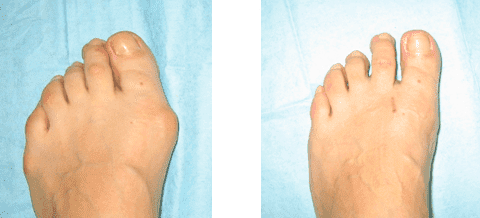

La mia gamba 1 mese dopo l'intervento

Raggi X delle gambe prima e dopo il trattamento

La mia gamba un mese dopo l'operazione

Le mie gambe un mese dopo l'intervento

Le mie gambe 9 mesi dopo l'intervento

Ecco come sono le mie gambe un anno dopo aver usato Artrosteel